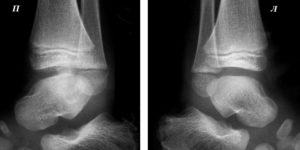

- Тип 2. Множественная дисплазия тазобедренных суставов. Клинические симптомы начинают обнаруживаться по достижении ребёнком возраста 2,5 лет. Он начинает предъявлять жалобы на боли в коленях и голеностопных суставах. Коленные суставы могут быть увеличены в размерах и деформированы. Эпифизы практически всех суставов уменьшаются в размерах и выглядят сглаженными.

- Тип 3. Самые первые симптомы этого типа дисплазии тазобедренного сустава начинают проявляться при достижении ребёнком пубертатного возраста. Походка у него становится «утиной» или «вперевалку». В коленных суставах развивается ограничение подвижности, начинают беспокоить боли. Ребёнок отличается низким ростом и короткими руками. Эпифизы бёдер сглажены, коленные суставы деформируются и увеличиваются в размерах. С течением времени развиваются признаки остеоартроза суставов.